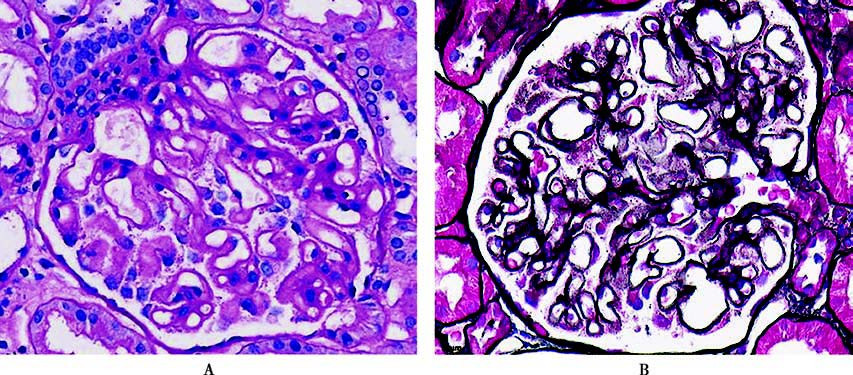

Figure 5 Pathological images of membranous nephropathy

A. Thickened and rigid glomerular basement membrane in light microscopy (PAS staining);

B. Thickened basement membrane with spike formation visible (silver staining).

In light microscopy, glomeruli exhibit diffuse lesions with generalized thickening of the capillary basement membrane. In the early stages, small scattered eosinophilic granules can be observed on the epithelial side of the glomerular basement membrane (GBM) using Masson staining. As the disease progresses, spike formations (visible with silver staining) appear, and the basement membrane thickens gradually. Immunofluorescence shows fine granular deposits of IgG and C3 along the glomerular capillary walls, sometimes accompanied by IgA and IgM deposits. Electron microscopy in the early stages reveals well-organized electron-dense deposits on the epithelial side of the GBM, often accompanied by widespread podocyte foot process effacement.